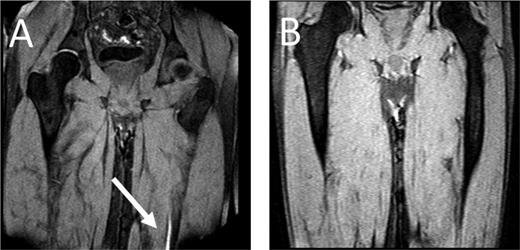

Direct thrombus imaging by magnetic resonance technique (MRDTI), a technique that is based on measurement of a shortening T1 signal as a result of the formation of methemoglobin in a fresh thrombus and does not require injection of contrast material such as gadolinium, has been shown to be a promising alternative for current diagnostic modalities for suspected ipsilateral recurrent DVT.15-18 The diagnostic accuracy of MRDTI for a first DVT is high (sensitivity, 97%-100%; specificity, 100%), the interobserver agreement between the 2 readers is excellent (κ = 0.98), and the signal is present within hours of thrombus formation and extinguishes completely after 6 months.15-17 The results from the RETURN study, in which MRDTI examination of 39 patients with confirmed recurrent DVT and 42 patients with residual thrombosis were compared with outcomes with compression ultrasound, clearly pointed out that MRDTI differentiates the 2 patient groups with great accuracy and reproducibility (sensitivity, 95%; specificity, 100%), with a negative predictive value of 95% (95% CI, 85-99) in this highly selected cohort with a recurrent DVT incidence of 48% (Figure 1).18 Based on this observation, it was hypothesized that MRDTI has equally high sensitivity but superior specificity than currently available ultrasonography techniques. To confirm this hypothesis, a prospective, multicenter management study, the Theia study, has started recently that will manage 305 patients with suspected ipsilateral recurrent DVT based on the result of MRDTI only, performed within 24 hours of clinical presentation (ClinicalTrials.gov identifier NCT02262052).19 All patients will be followed for the occurrence of symptomatic venous thrombosis during 3-month follow-up. In addition, cost-effectiveness and feasibility of MRDTI in clinical practice will be addressed.

MRDTI of patient from case 1 (A): the white arrow indicates the fresh thrombus in the popliteal vein of the right leg. For contrast, B depicts the MRDTI of a patient with residual thrombosis in the left popliteal and femoral vein: no DTI signal is present.

As for our patient, his Wells score for DVT indicated “likely probability” (total of 2 points, 1 point for “calf enlargement >3 cm compared with the other site” and 1 point for “pitting edema”), indicating that a D-dimer test could definitely not be used for ruling out DVT.6,20 Because the patient fulfilled all inclusion and none of the exclusion criteria for the Theia study, he was referred for MRDTI, which showed a clear signal in the right popliteal vein (Figure 1), confirming the diagnosis of recurrent ipsilateral DVT. After 6 months of treatment, a reference CUS was performed and showed persistent incompressibility of the right popliteal vein.